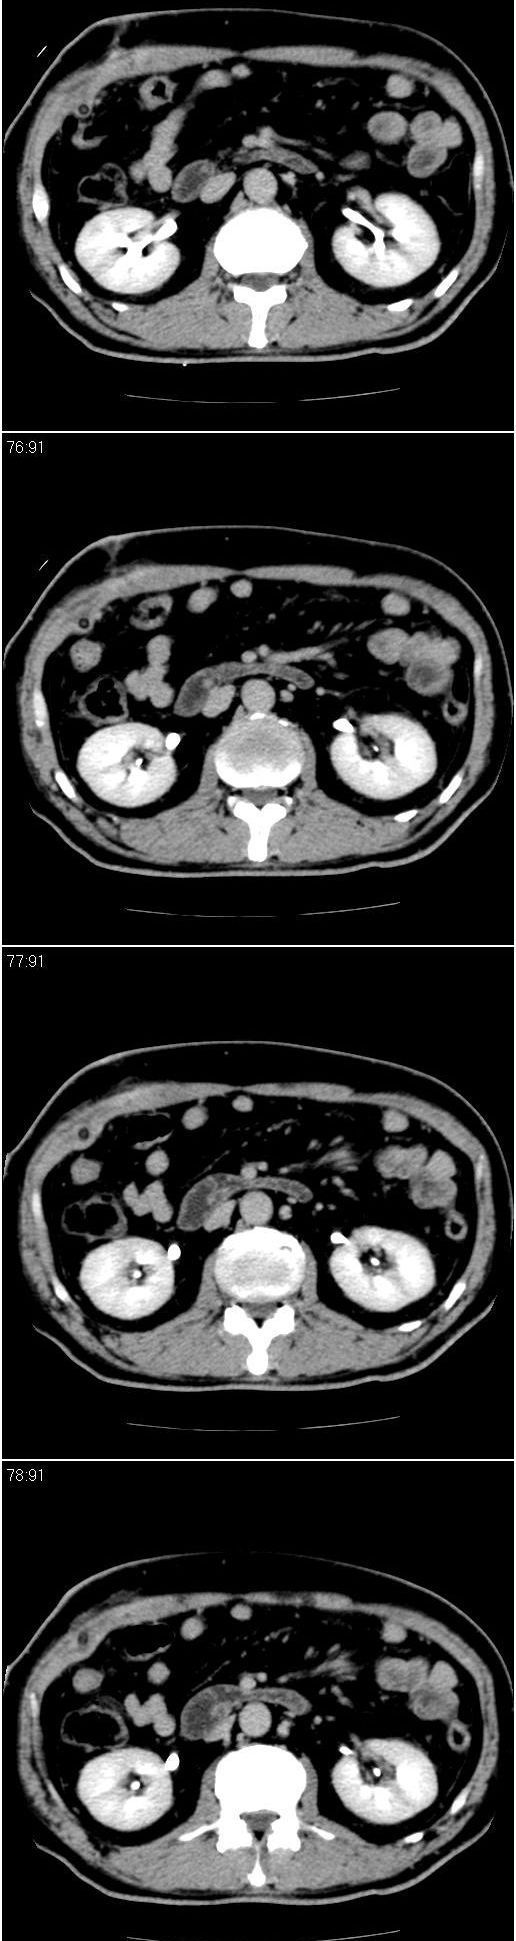

男,57岁。因胆结石阻塞性黄疸入院。这是胆囊切除术后的照片,看看此片到底有什么问题。

肝内外胆管轻度扩张,胆囊窝内见引流管考虑胆囊切除术后改变.胃窦部软组织似增厚,建议胃镜检查.

在手术切除胆囊的过程中,发现肝门部胆总管恶性占位,因为家属不同意手术,没有切除,能看出来么?

肝内外胆管轻度扩张。楼主提示左右肝管合汇区域壁稍厚。胆总管末段壁似也稍厚有轻度强化。就现有资料诊断难。